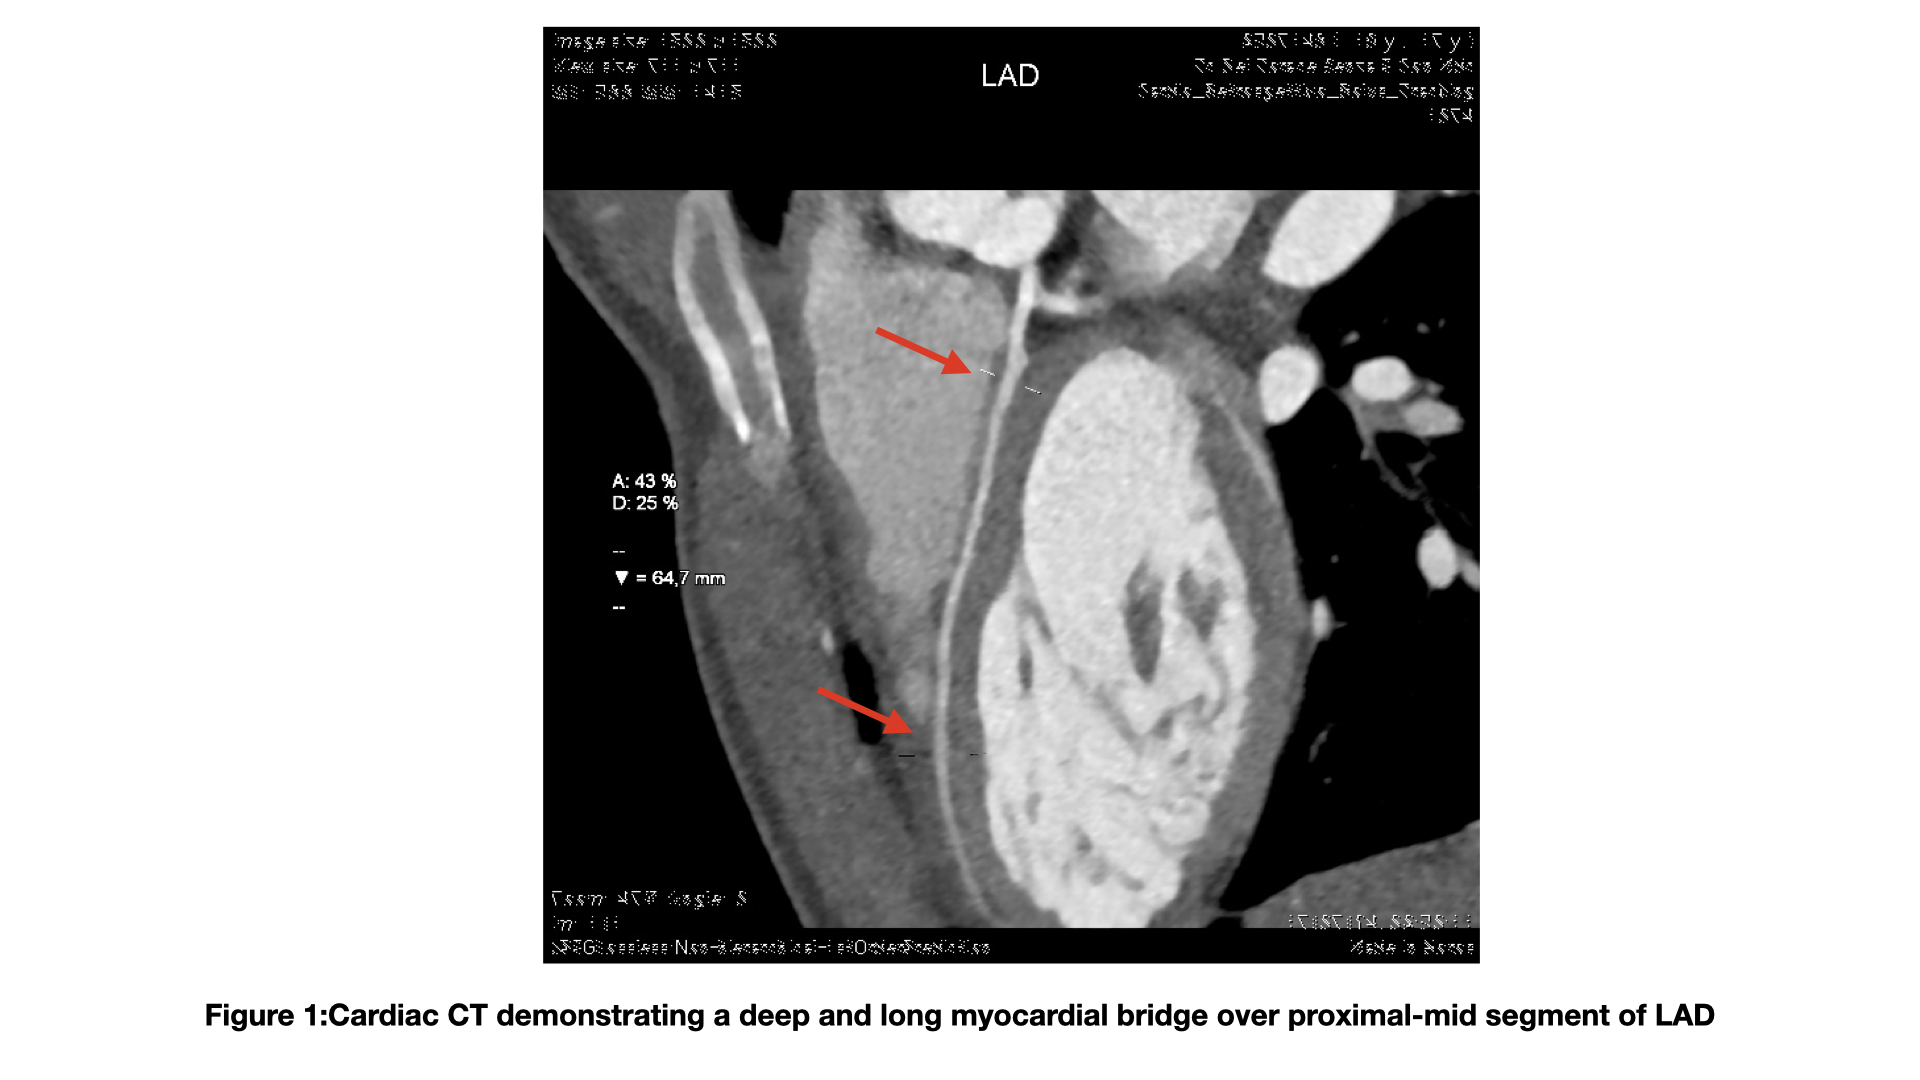

Background: Myocardial bridge (MB) is a tunneled segment of an epicardial coronary artery, running deep and for varying lengths in the context of the myocardial muscle. The clinical picture of MB ranges from the asymptomatic presentation to an acute coronary syndrome and sudden cardiac death. Case report : We present the case of a 18-year-old patient underwent pulmonary commissurotomy, cleft mitral valve closure and surgical correction of atrial septal defect when he was infant. During the recent follow-up, he experienced frequent ventricular extrasystoles organized into runs of non-sustained ventricular tachycardia during the exercise. Echocardiography demonstrated a normal biventricular function without severe residual valvular sequelae. No cardiomyopathy or late enhancement were detected by cardiac magnetic resonance evaluation. The patient was initially treated with beta-blocker and subsequently with amiodarone due to the persistence of arrhythmic burden during exercise. The diagnostic assessment was completed by coronary CT angiography, which revealed a long intramyocardial course of the left anterior descending artery, with length of 65 mm and maximum depth of about 3 mm. No significant luminal narrowing was observed during either systolic or diastolic phases; however, a filiform appearance of the vessel was noted in its distal segment. Following this radiological finding, the patient underwent functional evaluation with stress and rest myocardial scintigraphy, which demonstrated mild inducible ischemia involving the basal and parabasilar segments of the inferior and inferoseptal walls. According to the high anatomic risk features, we decide to assess the hemodynamic impact of MB with functional intracoronary evaluation. No systolic luminal narrowing was detected within the bridge segment like as no additional epicardial coronary abnormalities by coronary angiography (Fig.2).The invasive physiological assessment of MB was performed with RFR and FFR that were 0.93 and 0.9, respectively. The value of FFR remained unchanged after dobutamine intravenous infusion ( 20 μg/kg/min). Conclusion: This case highlights the use of FFR and RFR in assessing the functional impact of a MB. In this case,the patient was candidated to medical strategy increasing the beta-blocker and reducing the dose of amidoarone. Additionally, we have chosen precautionally to implant a loop recorder for monitoring the arrhythmic events; to date no repetitive events were detected.